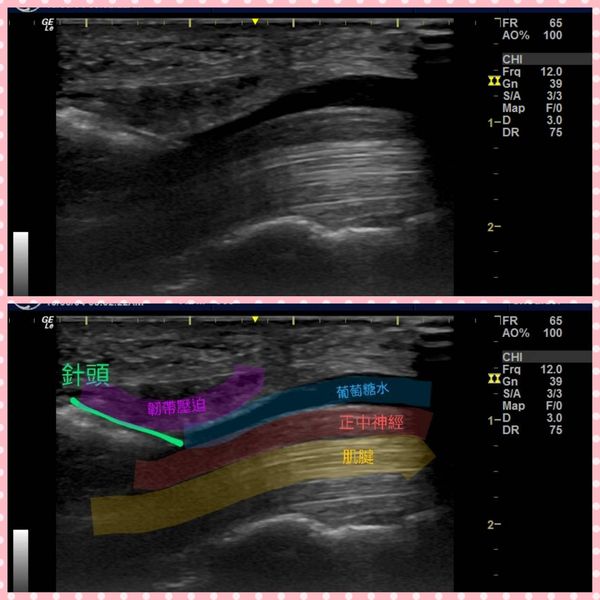

2、神經解套注射治療:利用超音波導引,注射葡萄糖水改善神經壓迫、降低神經發炎。

【請參考圖片二、三】